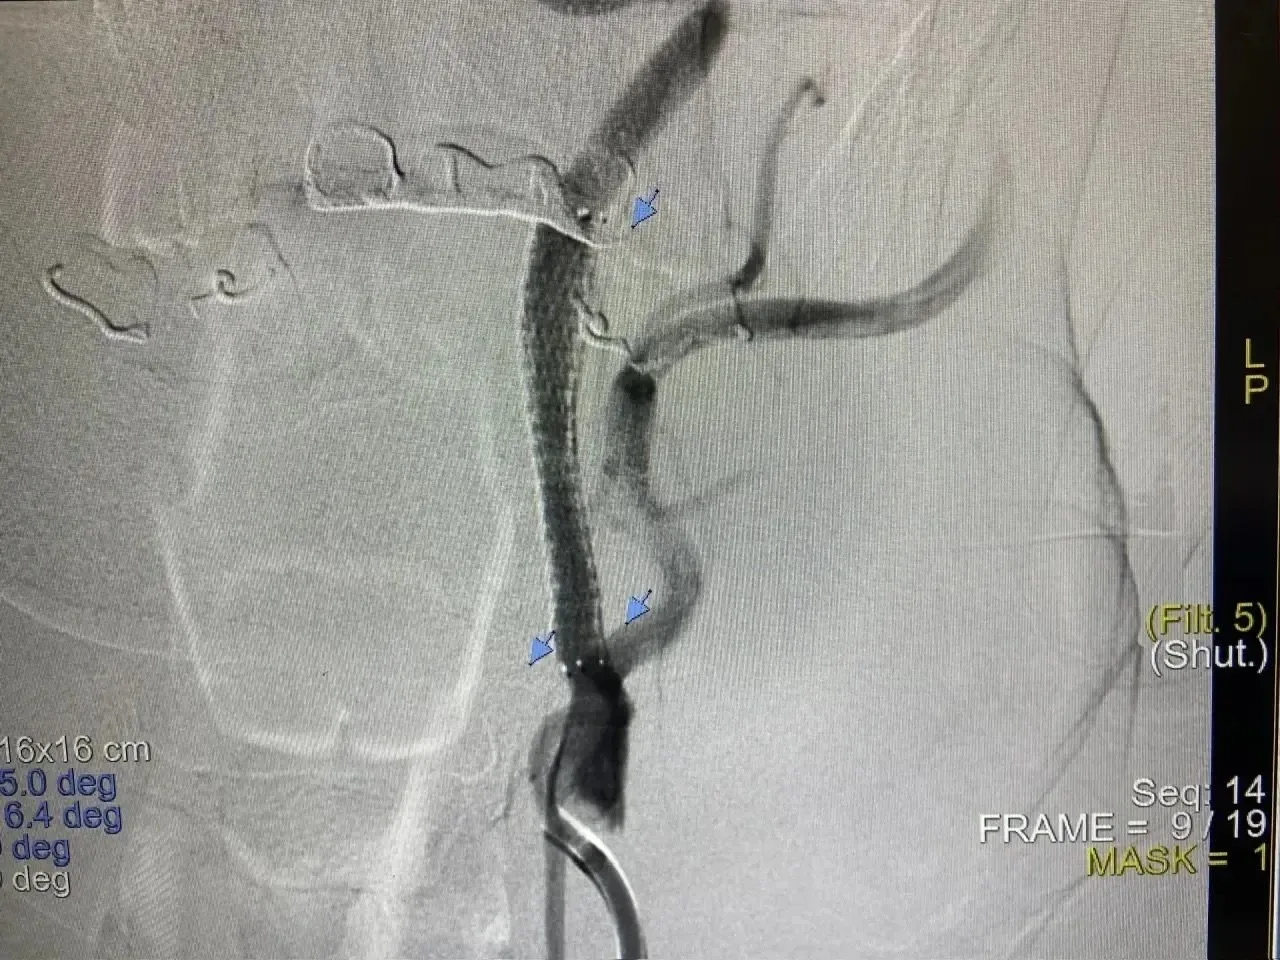

Пациентам было проведено стентирование сонных артерий — малоинвазивное вмешательство, которое позволяет восстановить проходимость магистральных сосудов, питающих головной мозг, при атеросклерозе. При обследовании медики диагностировали у пациентов большие стенозы внутренней сонной артерии - у одного пациента 90 %, у других более 80%, что затрудняло лечение, так как лекарство в головной мозг поступало неэффективно. Во всех случаях это уже повторный инсульт.